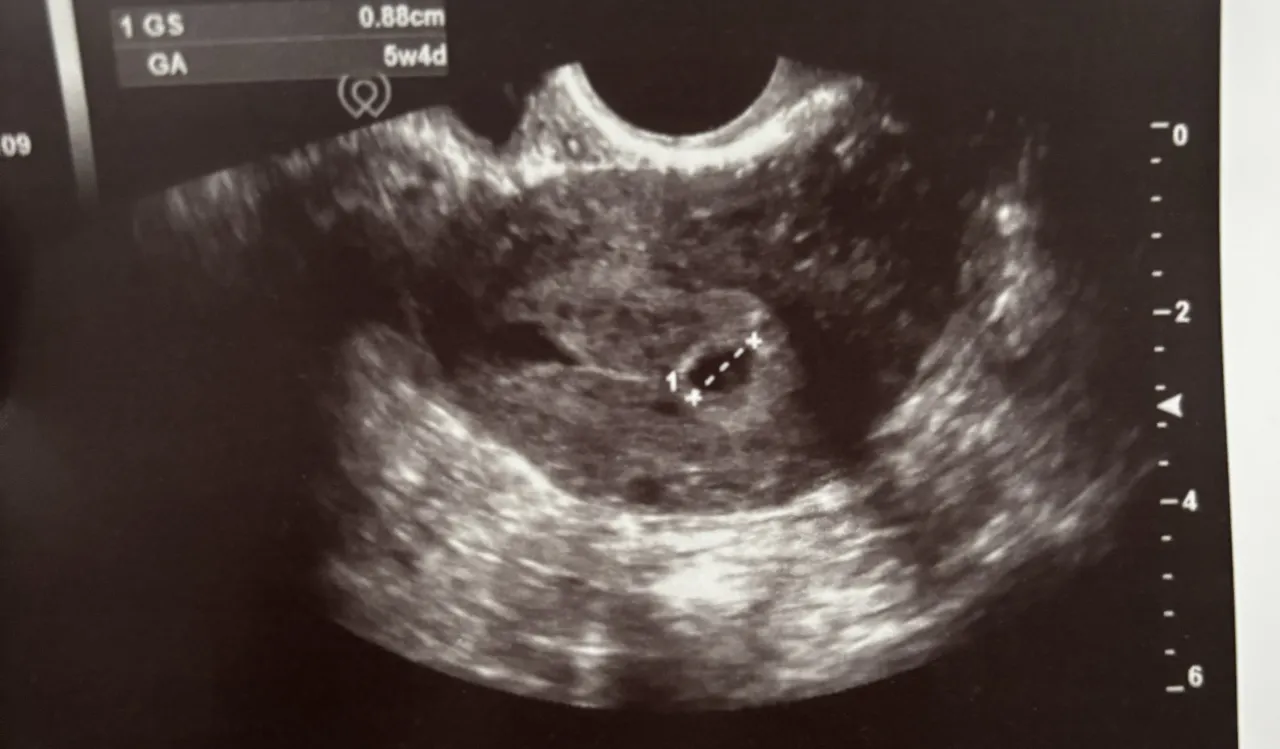

- Badanie USG w pierwszym trymestrze, szczególnie pomiar CRL, jest kluczowe do weryfikacji i korekty wieku ciąży, zwłaszcza przy nieregularnych cyklach.

Choć reguła Naegelego jest świetnym narzędziem do wstępnych obliczeń, to w dzisiejszej medycynie badanie ultrasonograficzne, szczególnie to wykonane w pierwszym trymestrze ciąży, odgrywa kluczową rolę w precyzyjnym ustalaniu wieku ciąży i weryfikacji terminu porodu. To właśnie USG pozwala nam zajrzeć do wnętrza i zobaczyć, jak rozwija się maluszek, dostarczając bezcennych danych.

Pomiar CRL (długości ciemieniowo-siedzeniowej) dlaczego jest "złotym standardem" na początku ciąży?

W pierwszym trymestrze ciąży, najdokładniejszym parametrem do oceny wieku ciąży jest pomiar długości ciemieniowo-siedzeniowej płodu (CRL Crown-Rump Length). To po prostu długość dziecka mierzona od czubka głowy do pupy. Dlaczego jest to "złoty standard"? Ponieważ w początkowych tygodniach ciąży wszystkie płody rozwijają się w bardzo zbliżonym tempie, niezależnie od genetyki czy innych czynników. Oznacza to, że dla danego CRL możemy z dużą precyzją określić wiek ciążowy. Ta metoda jest najbardziej dokładna do około 10. tygodnia ciąży. Po tym okresie tempo wzrostu zaczyna się indywidualizować, a inne parametry (takie jak obwód głowy, brzucha, długość kości udowej) stają się bardziej miarodajne, ale już z nieco mniejszą precyzją w kontekście datowania ciąży. Dlatego tak ważne jest wykonanie pierwszego USG w odpowiednim czasie.

"Złotym standardem" jest wtedy pomiar długości ciemieniowo-siedzeniowej płodu (CRL), który jest najdokładniejszy do 10. tygodnia ciąży.

Czy USG może zmienić Twój termin porodu? Kiedy lekarz koryguje datę